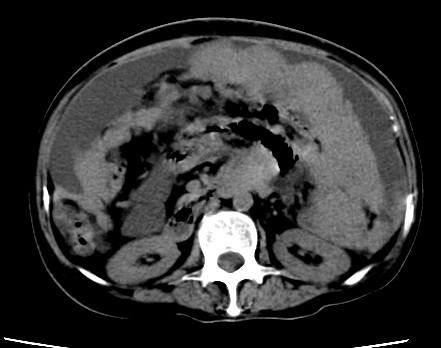

标题: CT23975:女61岁,腹部不适,明显消瘦

既往5年前卵巢癌行子宫及附件切除,右乳癌术后一年,考虑腹膜转移?

支持楼主!(腹膜 网膜均有转移)

1)结合病史,考虑腹膜及网膜转移瘤。2)肝脏多发性低密度灶,不排除转移瘤。3)大量腹水。

考虑卵巢癌行子宫术后复发,并肝、腹腔 、大网膜转移可能性大。

大量腹水。